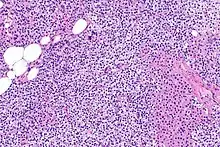

El hiperparatiroidismo, en general, está causado por el crecimiento tumoral en una o más glándulas de paratiroides o una disminución prolongada en niveles de calcio de la sangre o hipocalcemia que a su vez estimula la producción y liberación de hormona del paratiroides de la glándula de paratiroides.[10][11] Las glándulas paratiroides están localizadas junto a la glándula tiroides en el cuello, por debajo y delante de la laringe y por encima de la tráquea. Generalmente se compone de cuatro glándulas que regulan los niveles de calcio en sangre a través de receptores sensibles a calcio anclados a una proteína G.[12] La función principal de estas glándulas es la homeostasis del calcio.[13] Histológicamente, están compuestas de células principales y oxifílicas, siendo las células principales las principales responsables del almacenamiento y liberación de hormona paratiroidea. Estas células están dispuestas en un patrón pseudofolicular similar a los folículos tiroides. La tinción de queratina se utiliza para ver los gránulos de hormona paratiroidea.[9][14]

La hiperplasia primaria de la glándula paratiroides se debe tanto a la hipocalcemia como al aumento de los niveles de fosfato al disminuir la expresión de los receptores de vitamina D en la glándula paratiroidea.[8][4] Esta disminución en la expresión de receptores conduce a un hiperfuncionamiento de la paratiroides. Se cree que la hiperfunción de la glándula paratiroidea exacerba la hiperplasia primaria que evoluciona a una hiperplasia secundaria más agresiva. Histológicamente, estas glándulas pueden ser difusas o nodulares.[24] La hiperplasia primaria, que por lo general se trata de un crecimiento policlonal difuso, está relacionada con el hiperparatiroidismo secundario reversible. La hiperplasia secundaria de la glándula paratiroides es más a menudo un crecimiento monoclonal nodular que sostiene el hiperparatiroidismo secundario y es el catalizador en la progresión al hiperparatiroidismo terciario. Las glándulas hiperplásicas nodulares en el hiperparatiroidismo terciario son claramente más grandes tanto en tamaño absoluto como en peso. Se han informado de aumentos de 20 hasta 40 veces.[25][26]

Las glándulas paratiroides están normalmente compuestas de células principales, adipocitos y células oxifílicas esparcidas.[27][14] Se piensa que las células principales son las responsables de la producción, almacenamiento y secreción de hormona paratiroides. Estas células aparecen claras y oscuras con un aparato de Golgi prominente y retículo endoplásmico. En micrografías con microscopio electrónico, las vesículas secretoras se pueden ver dentro y alrededor del aparato de Golgi y en la membrana celular. Estas células también contienen grasa citoplásmica prominente. Al inicio de la hiperplasia, estas células están descritas formando un patrón nodular con aumento de la maquinaria de síntesis de proteínas como el retículo endoplásmico y el aparato de Golgi. También se aumenta el número de vesículas secretoras que puede ser vistas y disminuye la grasa intercelular.[24] Las células oxifílicas también parecen hiperplásicas, sin embargo, estas células son mucho menos prominentes.